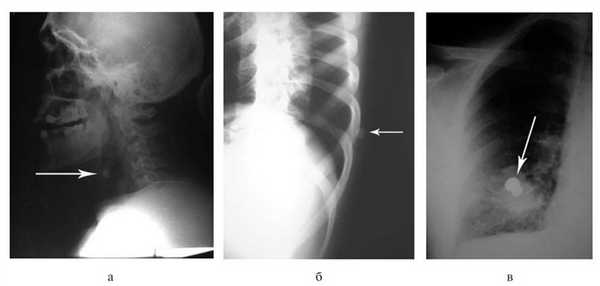

Поверхностные раны шеи требовали первичной хирургической обработки с экономным иссечением их краев. Инородных тел в тканях при этом не выявлено. При глубоком ранении (что определялось по внешнему виду раны) для исключения повреждения органов и структур шеи выполняли обзорную рентгенографию (рис. 4, а), Рисунок 4. Обзорные рентгенограммы пострадавших с ранениями из травматического оружия. Стрелками указаны инородные тела (пули). а - при ранении шеи; б - при непроникающем ранении груди; в - при проникающем ранении груди. затем продольную переднюю колотомию (21 наблюдение). При этом в 1 наблюдении обнаружено ранение трахеи и в 2 - повреждение ротоглотки. Инородные тела извлечены в 10 наблюдениях (пули из пистолета «Макарыч» - в 6, из «Осы» - в 4). Хирургическая обработка раневого канала являлась заключительным этапом вмешательства.

При поступлении пострадавших с ранениями груди и живота, причиненными травматическим оружием, выполняли обзорную рентгенографию. У 217 больных ранения были непроникающими (рис. 4, б). Следует подчеркнуть, что пули калибра 9 мм являются малоконтрастными и определение их локализации при рентгенологическом исследовании представляло определенную трудность.